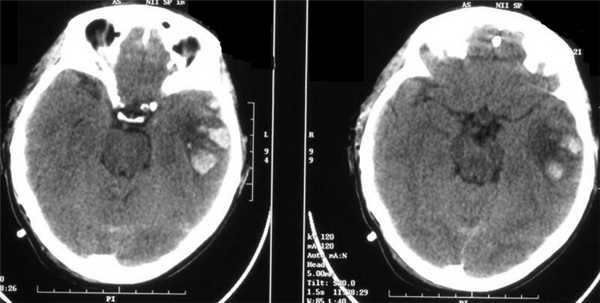

Острая субдуральная гематома (оСДГ) малых размеров, но при этом визуализируется непропорциональный повреждению масс-эффект. Степень смещения срединных структур (подфальксное вклинение) больше, чем характерно для острой субдуральной гематомы. Отек ипсилатерального полушария головного мозга. Развитие отека мозга может быть внезапным и стремительным.

С точки зрения наличия структурных повреждений мозга по данным методов нейровизуализации ЛЧМТ включает в себя: сотрясение - наиболее лёгкая клиническая форма диффузного транзиторного повреждения мозга, в основе которого лежат метаболические, ионные, нейротрансмиттерные нарушения и нейровоспаление, характеризующаяся отсутствием изменений на КТ и МРТ; и ушиб мозга лёгкой степени (1 вида) - форма ЛЧМТ, характеризующаяся минимальным очаговым повреждением вещества мозга с макроструктурными изменениями (ограниченные разрывы пиальных сосудов, мелкие геморрагии, локальный отёк мозга), наличием гиподенсивной зоны на КТ-томограммах или однородными очаговыми изменениями интенсивности сигнала в соответствующих режимах МРТ. Ушиб мозга лёгкой степени происходит в результате как непосредственного воздействия механической энергии на вещество мозга, так и удара о противолежащие стенки черепа или большой серповидный отросток, мозжечковый намёт.

При ушибе мозга лёгкой степени возможны переломы костей свода черепа и субарахноидальное кровоизлияние. КТ в половине наблюдений выявляет в мозговом веществе ограниченную зону пониженной плотности, близкую по денситометрическим показателям к отёку головного мозга (от 18 до 28 Н). При этом возможны, как показали патологоанатомические исследования, точечные диапедезные кровоизлияния, для визуализации которых недостаточна разрешающая способность КТ. В другой половине наблюдений ушиб мозга лёгкой степени не сопровождается очевидными изменениями КТ картины, что связано с ограничениями метода. Отёк мозга при ушибе лёгкой степени может быть не только локальным, но и более распространённым. Он проявляется умеренным объёмным эффектом в виде сужения ликворных пространств. Эти изменения обнаруживаются уже в первые часы после травмы, обычно достигают максимума на 3 сутки и исчезают через 2 недели, не оставляя следов. Локальный отёк при ушибе мозга легкой степени может быть также изоденсивным, и тогда диагноз основывается на объёмном его эффекте, а также результатах динамики КТ.